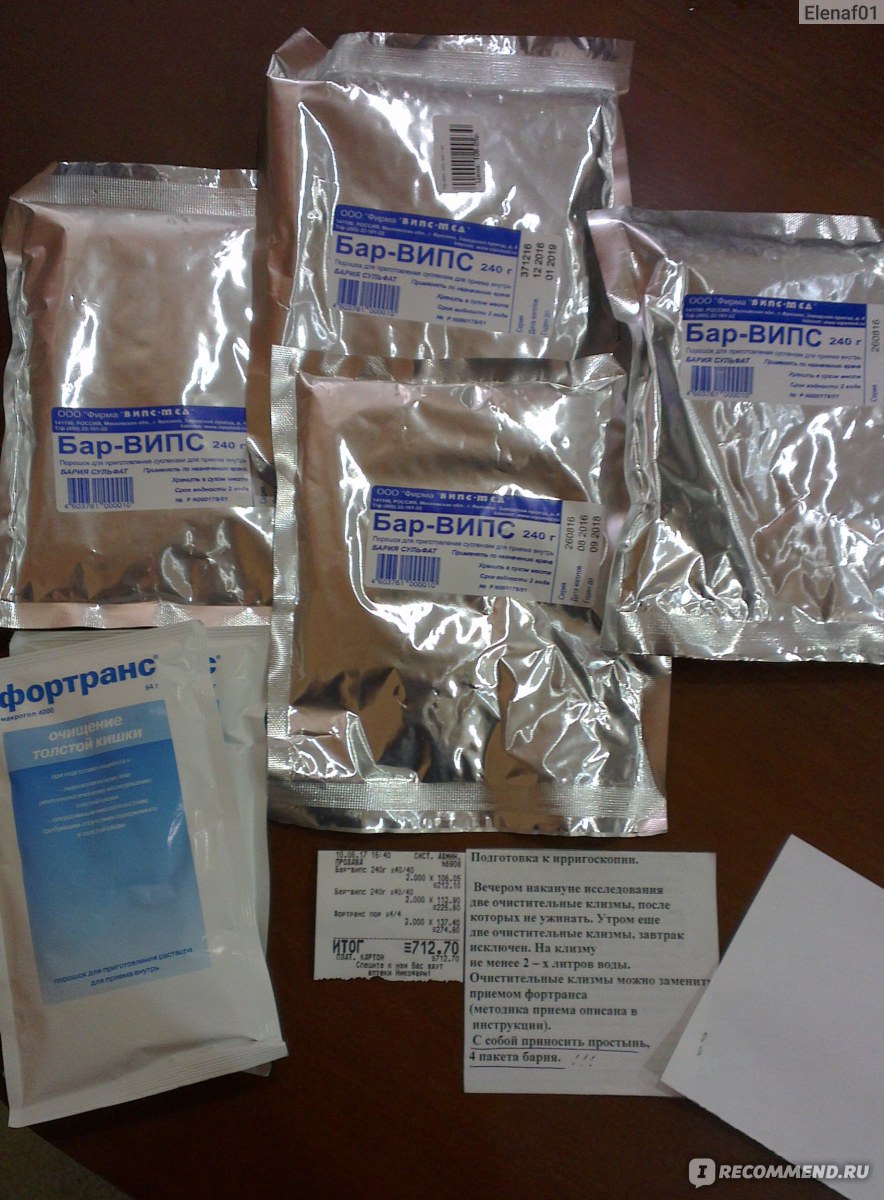

Подготовка к ирригоскопии: необходимые препараты